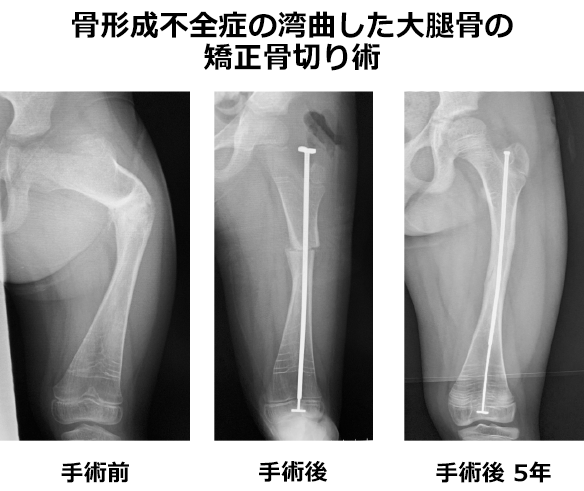

骨形成不全症

骨形成不全症は、骨系統疾患の中に分類され、日本整形外科学会骨系統疾患全国登録では登録数が最多(13.1%)です。顔面の特徴、身長、単純X線による全身の検査により診断しますが、軽症型の方は遺伝子診断が必要になります。

病態は、Ⅰ型コラーゲンの質的量的異常で、軽症型から重症型まであり、四肢の変形・関節機能障害・側彎症・低身長など骨格の障害が目立ちます。整形外科では、リハビリテーション、補装具治療、症状によっては手術治療が必要です。

骨折頻度を少なくする為に、「骨形成不全症の診療ガイドライン」(日本小児科学会雑誌.2006年)を基準にしてパミドロン酸二ナトリウムの点滴治療を行っています。特にSillence分類typeⅢなどで、骨の変形が強く立位、歩行に支障を来す場合には、AESCULAP ®︎ telescopic rod(ステンレス製)などを用いて変形矯正骨切り術を行います。